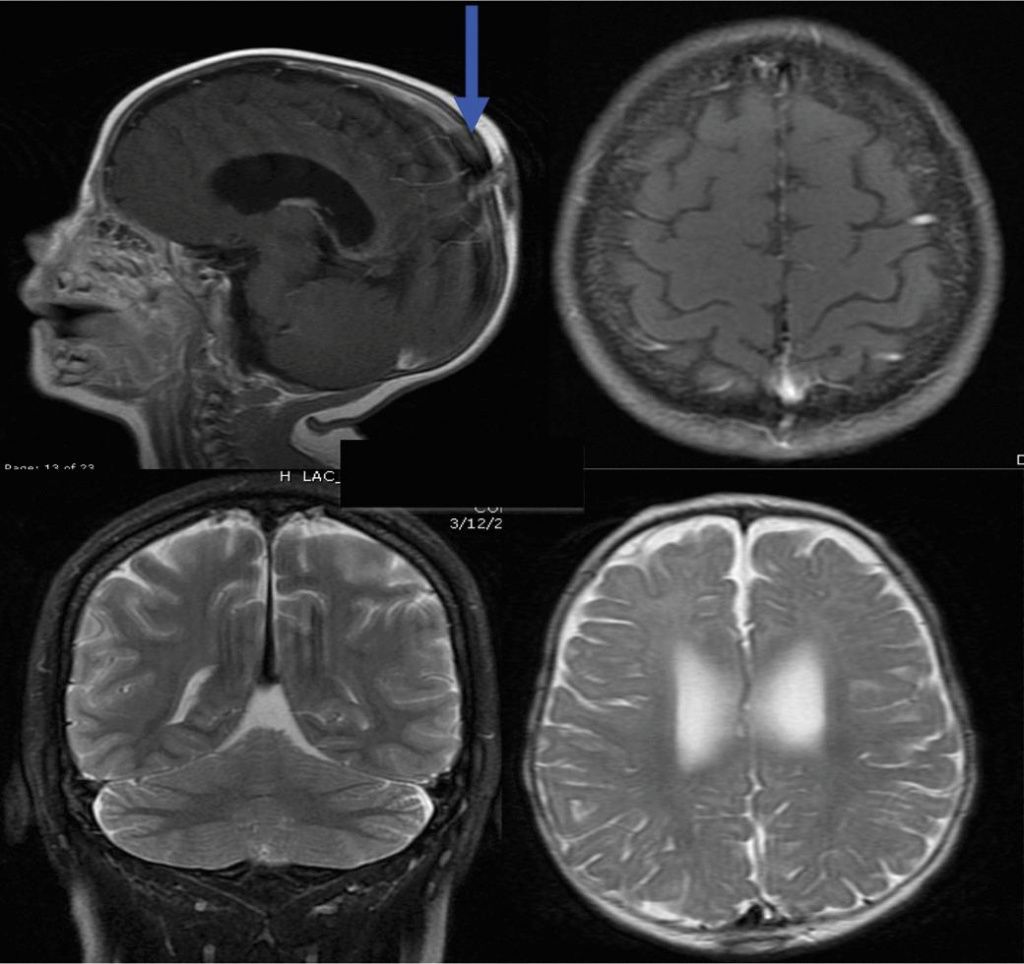

МРТ головного мозга: Расшифровка снимков и Интерпретация

Раздел: Визуальные уроки